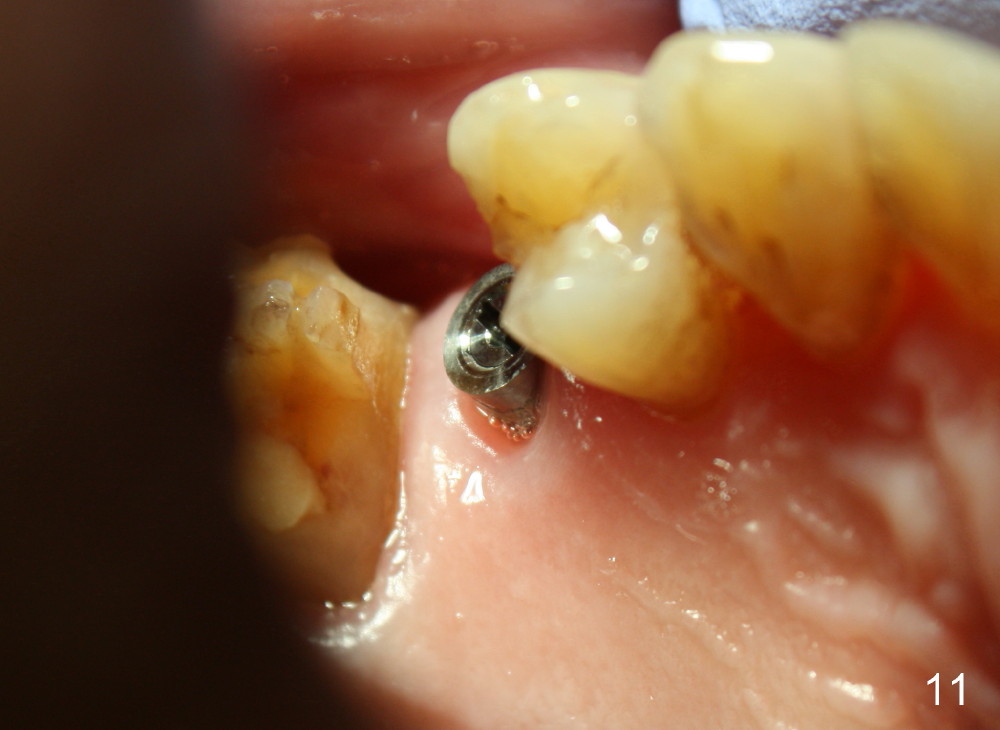

A 72-year-old man is a bruxer with #3 cusp fracture with chronic periapical radiolucency (Fig.1 *) and #4 acute crack. It appears reasonable to take care of emergency (#4 extraction and immediate implant (Fig.3-7: 4.5x20 mm, 45 Ncm)) followed by root canal therapy or extraction for #3. Eight (Fig.8) and 14 (Fig.9-11) days postop, the patient is doing fine and the wound heals normally. But he does not agree any treatment for #3, since it is asymptomatic in spite of a fistula associated with the tooth (Fig.8,9 >). Three months postop, the patient is still asymptomatic and is ready for #4 restoration since the tooth #28 cracks. Follow-up PA shows the persistent distal gap (Fig.12 >, as compared to Fig.4), accompanied with crestal bone resorption (*). Clinically the implant has mild mobility and light tenderness. The patient still refuses #3 treatment. It appears that the implant has failed to osteointegrate. In brief, do not place an immediate implant next to active infection.